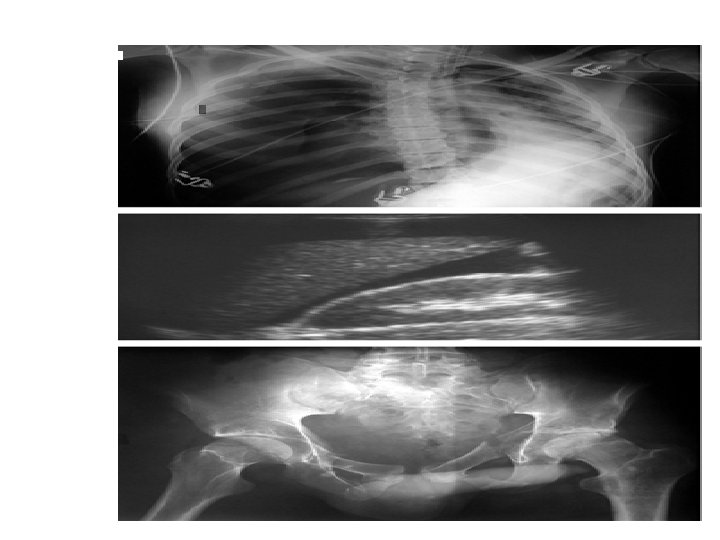

STRATEGIE DES EXAMENS PARACLINIQUES

Fast echo ?